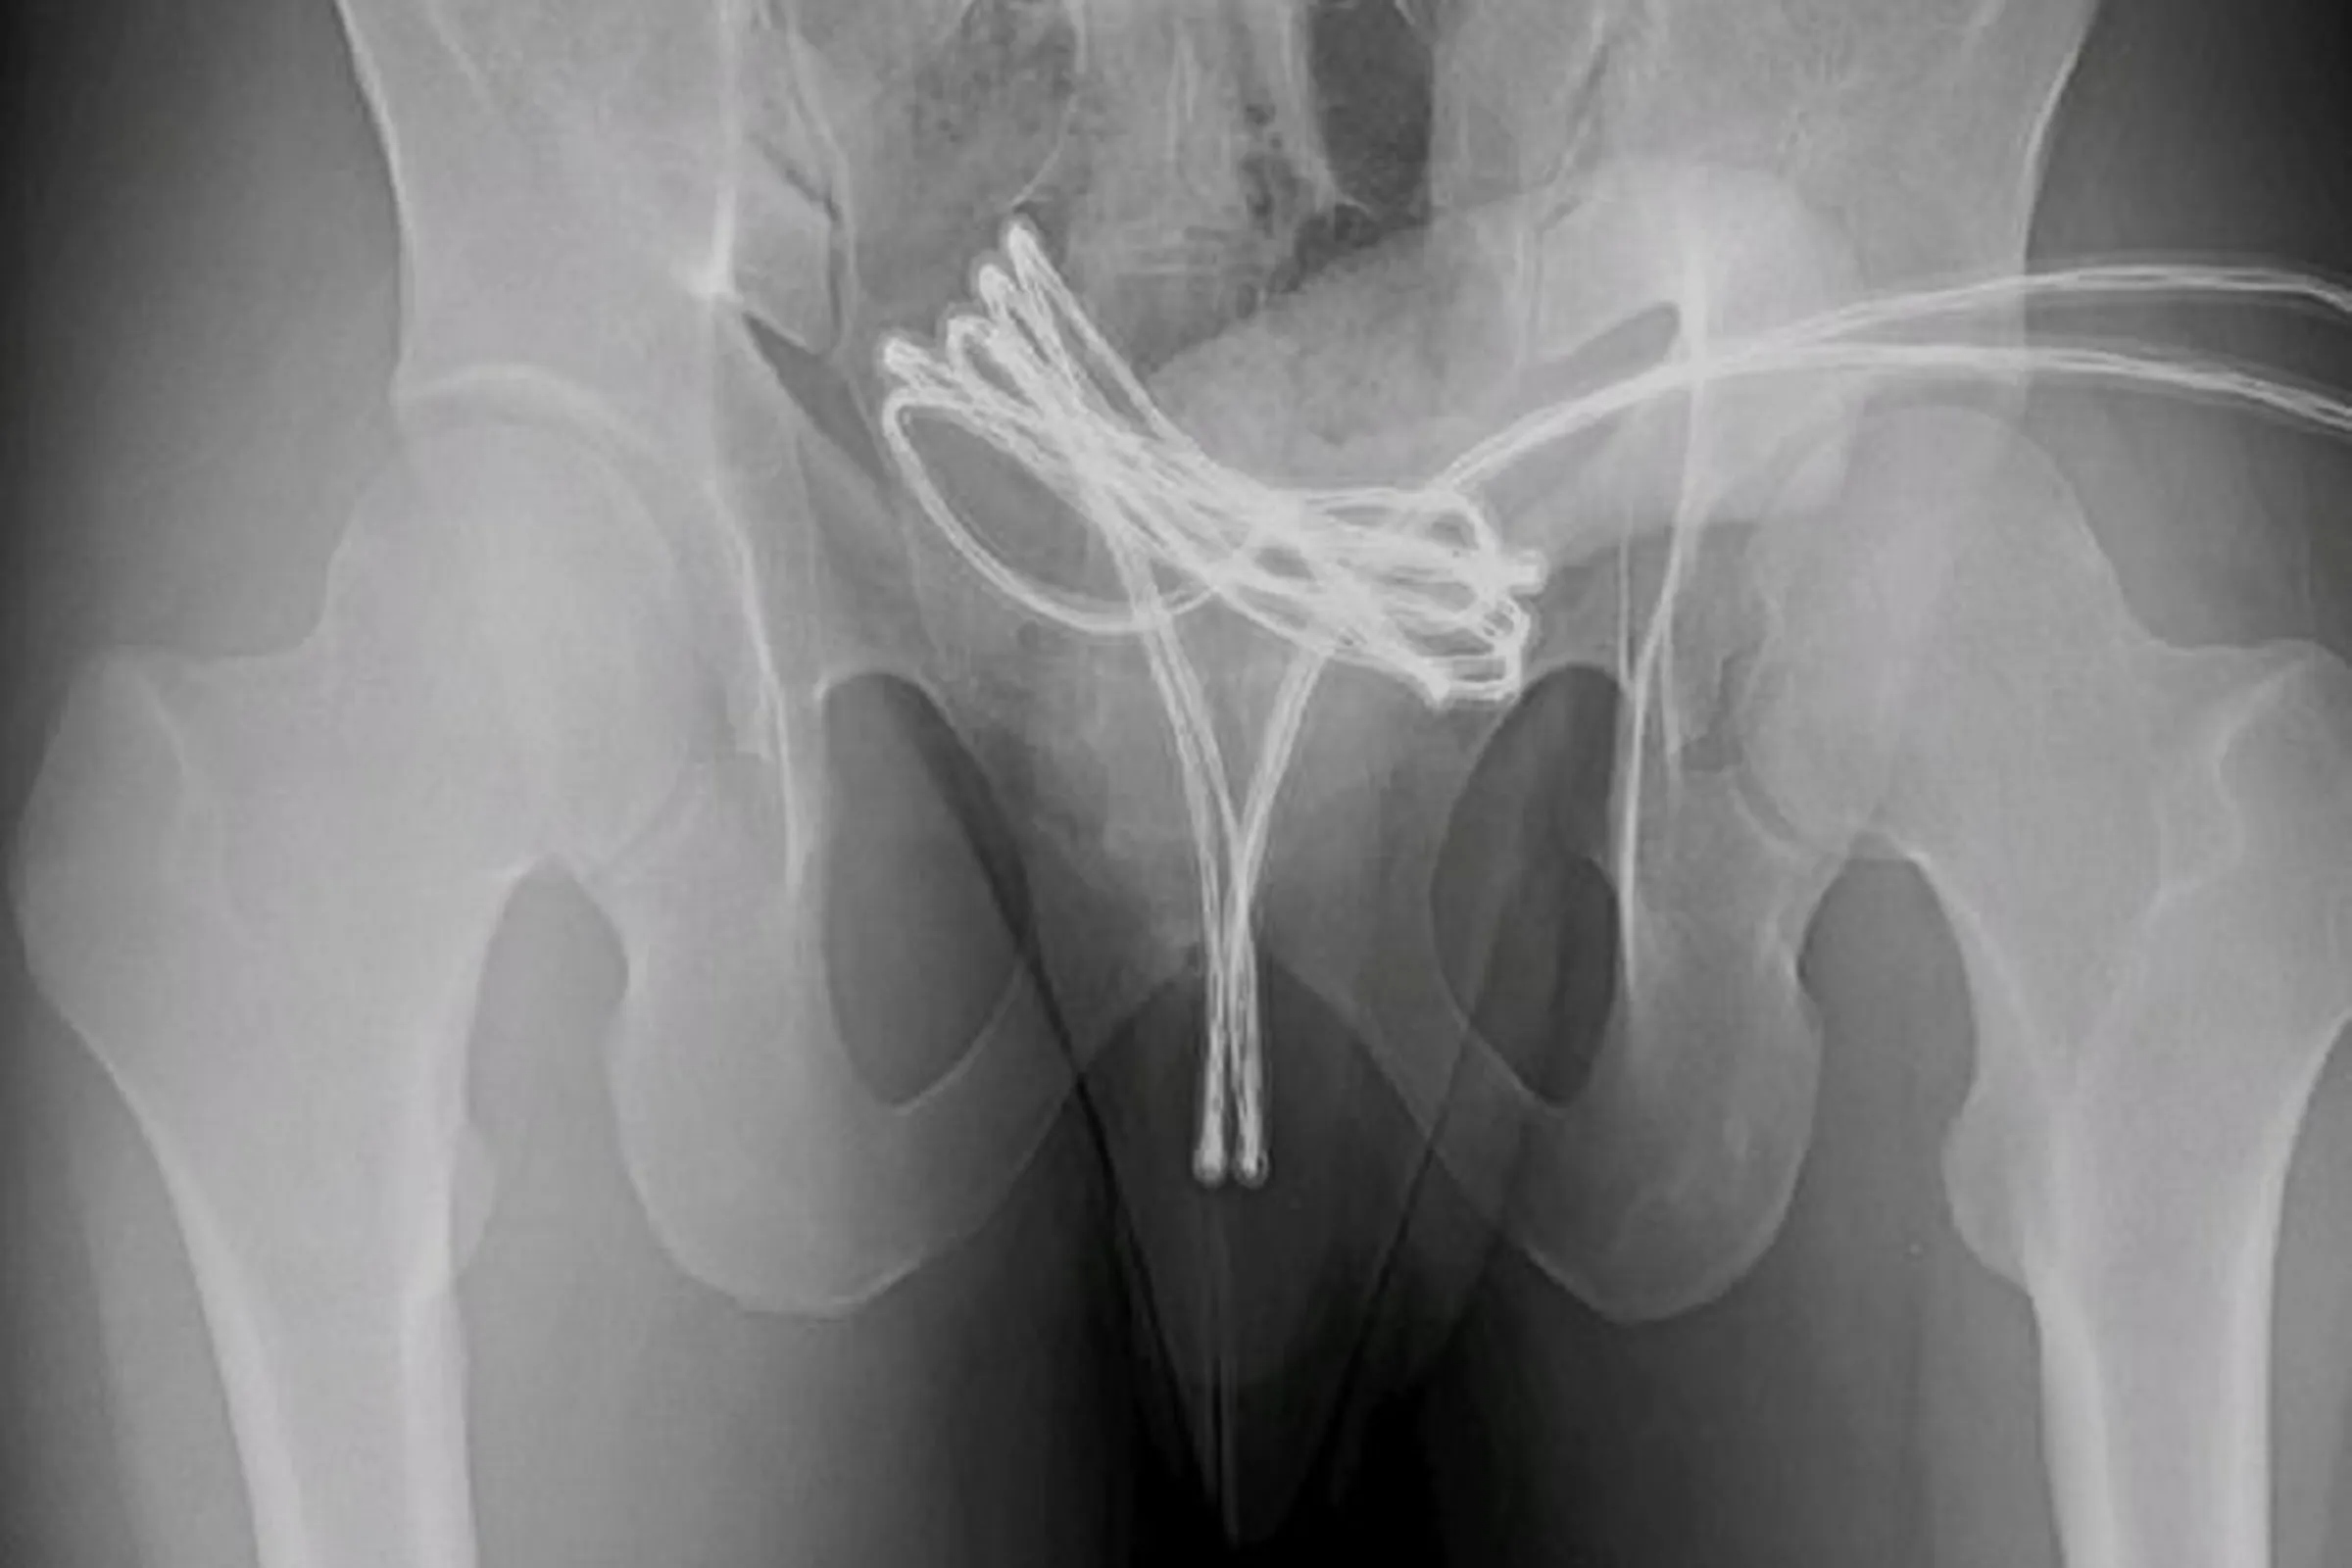

與USB線刺激愛愛,整條卡進下體突破膀胱!尷尬影像曝光。圖/翻自《Cureus》

醫學期刊《Cureus》近日刊登一起美國醫師的報告案例,一名21歲男子掛急診,原因竟是整條USB線卡在下體,並纏住膀胱。男子也承認,自己和這條USB線有過激烈愛愛。

報告指出,這名男子掛急診時,被檢查出一條長長的USB線已經穿過尿道,進入了膀胱,甚至快要纏住膀胱。醫師本來試圖徒手取出,但後來發現無法成功,因此只好先將男子麻醉,利用醫療工具將這條USB線取出。最後醫師成功將USB線取出,並讓男子住院1週觀察,待男子狀況穩定後,讓男子回家休養,並開立止痛藥與抗生素給男子服用。